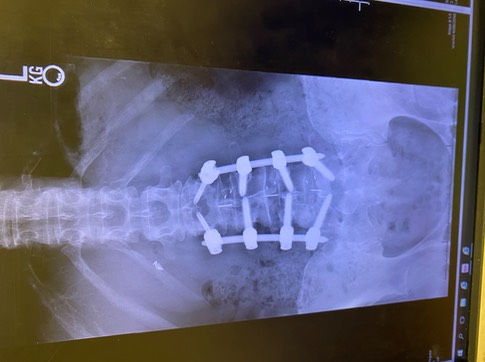

Honestly looking at the x-rays (Disclaimer* below is a picture of the x-ray showing the hardware), was a bit of a shock. While I knew as a nurse what had been place, it’s quite different to see the result. I wonder if Wolverine (X-Men) felt the same when he looked at what had been implanted in him? I’ve been asked if I can feel the hardware. Yes and No. Right now, I cannot feel the hardware if I run my fingers down my scar, that will probably change as inflammation continues to go down, due to my body structure. What I can feel is an odd sensation that is made up of muscles healing (they were cut during surgery) and a brick-like feeling, which is the hardware. There is a strange feeling as well which is the inability of that section of my spine to move.